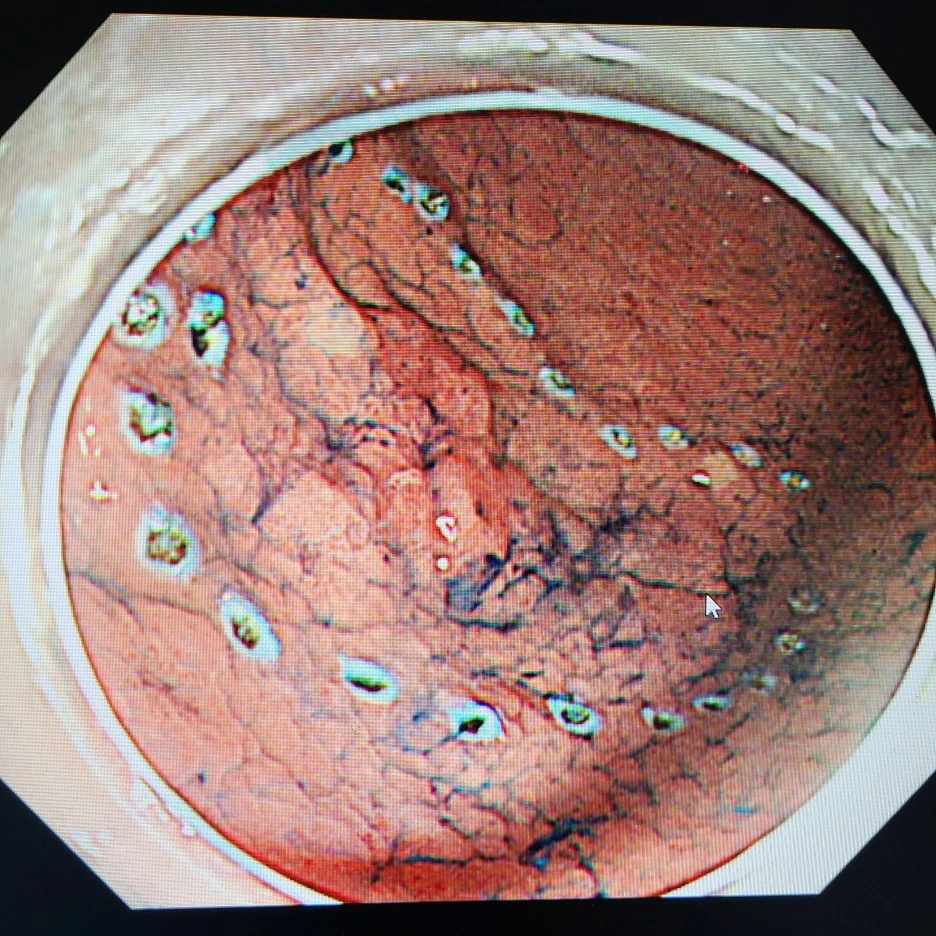

KakaoTalk_20211219_215906391_03.jpg?type=w1 표시를 했는데 하트가?

이것은 시술할 부위를 marking(표시)를 한 사진인데 저 마킹한 테두리를 따라서 precut(표시한 테두리를 따라 자르는 것)을 한 뒤에 dissection(절개)를 시작한다. 중간의 빨간 부분은 암으로 진단된 병변 부위이고 파란색은 인디고 카민(지시약)이 뿌려진 모습인데 점막 부분의 요철을 채워서 병변과 정상 점막을 더 쉽게 비교할 수 있게 해준다. 시간이 지나서 씻기고 중력 방향으로 흘러서 사진상엔 병변의 단차가 잘 표시 나진 않지만 병변을 더 명확하게 파악할 수 있게 해준다.

지금 하고 싶은 이야기는 인디고 카민이나 병변 부위나 시술의 순서가 아니라 테두리를 표시한 사진이 하트 모양이라는 것이다. 오늘 하트를 봤다며 보여 줬지만 아내는 냉정하게 한 마디 했다.

나름 신기하다며 하트를 보여 줬지만 이걸 보고 신나하고 신기해할 사람은 내시경실에서 일하는 사람이 전부일 것이다. 확실히 내 폰의 사진첩은 시우 사진과 내시경 병변 사진으로 가득 차 있으며 처음 보는 사람은 붉고 빨간 점막들과 병변들 사진들에 기겁을 한다. 5cm이 넘는 mapping(제거된 병변을 처음 있었던 모양처럼 펴서 고정하는 일) 된 사진 들과 조직 검사 결과를 확인하기 위해 수많은 내시경 사진들이 핸드폰에 저장되어 있다. 그때도 resection margin(절제면)이 하트 모양 같다고 아내에게 보여줬다가 징그럽다며 한소리를 들었다. 물론 내가 사이코 패스에 공감 능력이 제로인 남자는 아니다. 병변이 신기하게 하트 모양이라서 보여주고 싶었을 뿐이다.